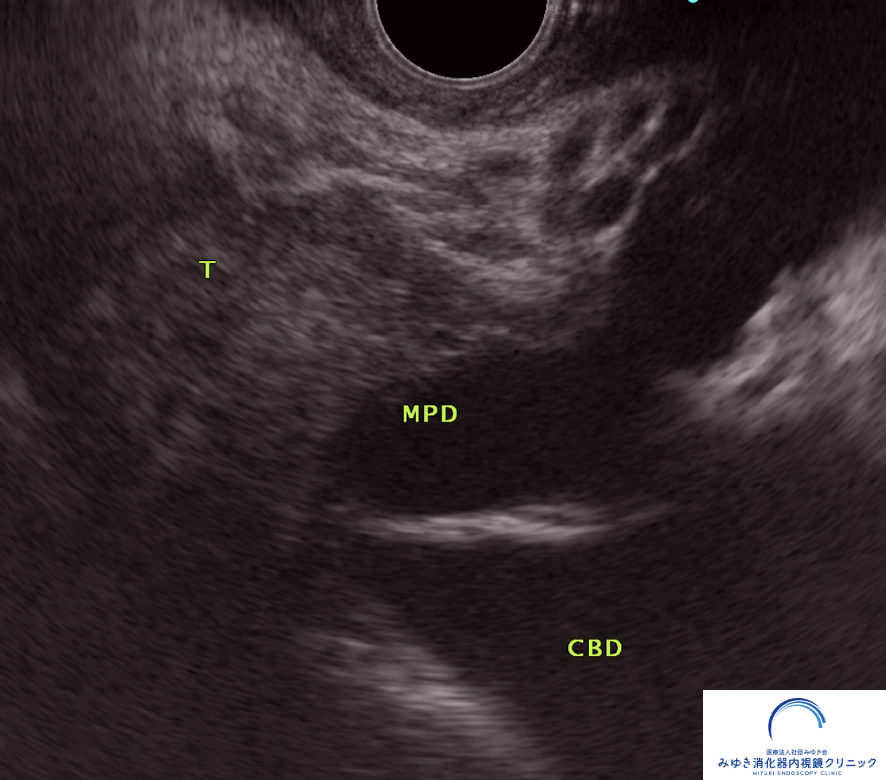

なぜ超音波内視鏡(EUS)が有効なのか

超音波内視鏡(EUS)は、内視鏡の先端に超音波装置がついた検査で、

胃や十二指腸の内側から膵臓を詳しく観察することができます。

膵臓に近い位置から観察できるため、

CTやMRIでは見えにくい小さな病変も描出できるのが特徴です。

他院の腹部エコーおよびCTで膵管拡張を指摘され、当院で超音波内視鏡(EUS)による精密検査を行いました。

他院の腹部エコーおよびCTで膵管拡張を指摘され、当院で超音波内視鏡(EUS)による精密検査を行いました。 膵臓に約8mmの腫瘍を認め、手術の結果、ステージ1の膵がんと診断されました。 通常の検査では見つかりにくい小さな病変が、EUSによって早期発見につながった症例です。

このように、通常の検査では見つかりにくい小さな膵がんも、EUSによって発見できることがあります。